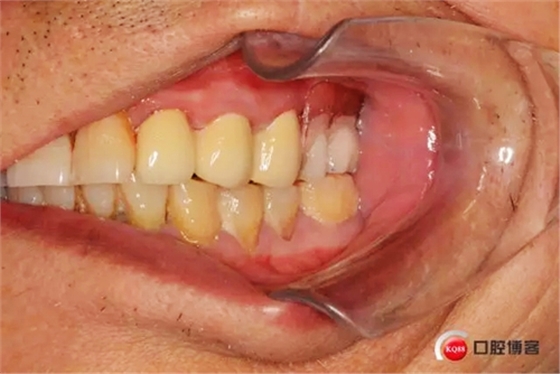

1498574625_742835.jpg

樁核帶入口腔情況

制作完成的義齒,22號(hào)牙前伸合有創(chuàng)傷調(diào)出金屬不影響美觀沒(méi)有修復(fù)

1498574637_437653.jpg

戴入口腔的合面觀,患者下頜缺失7,因單端合力問(wèn)題此牙也沒(méi)有修復(fù)7

咬合情況.